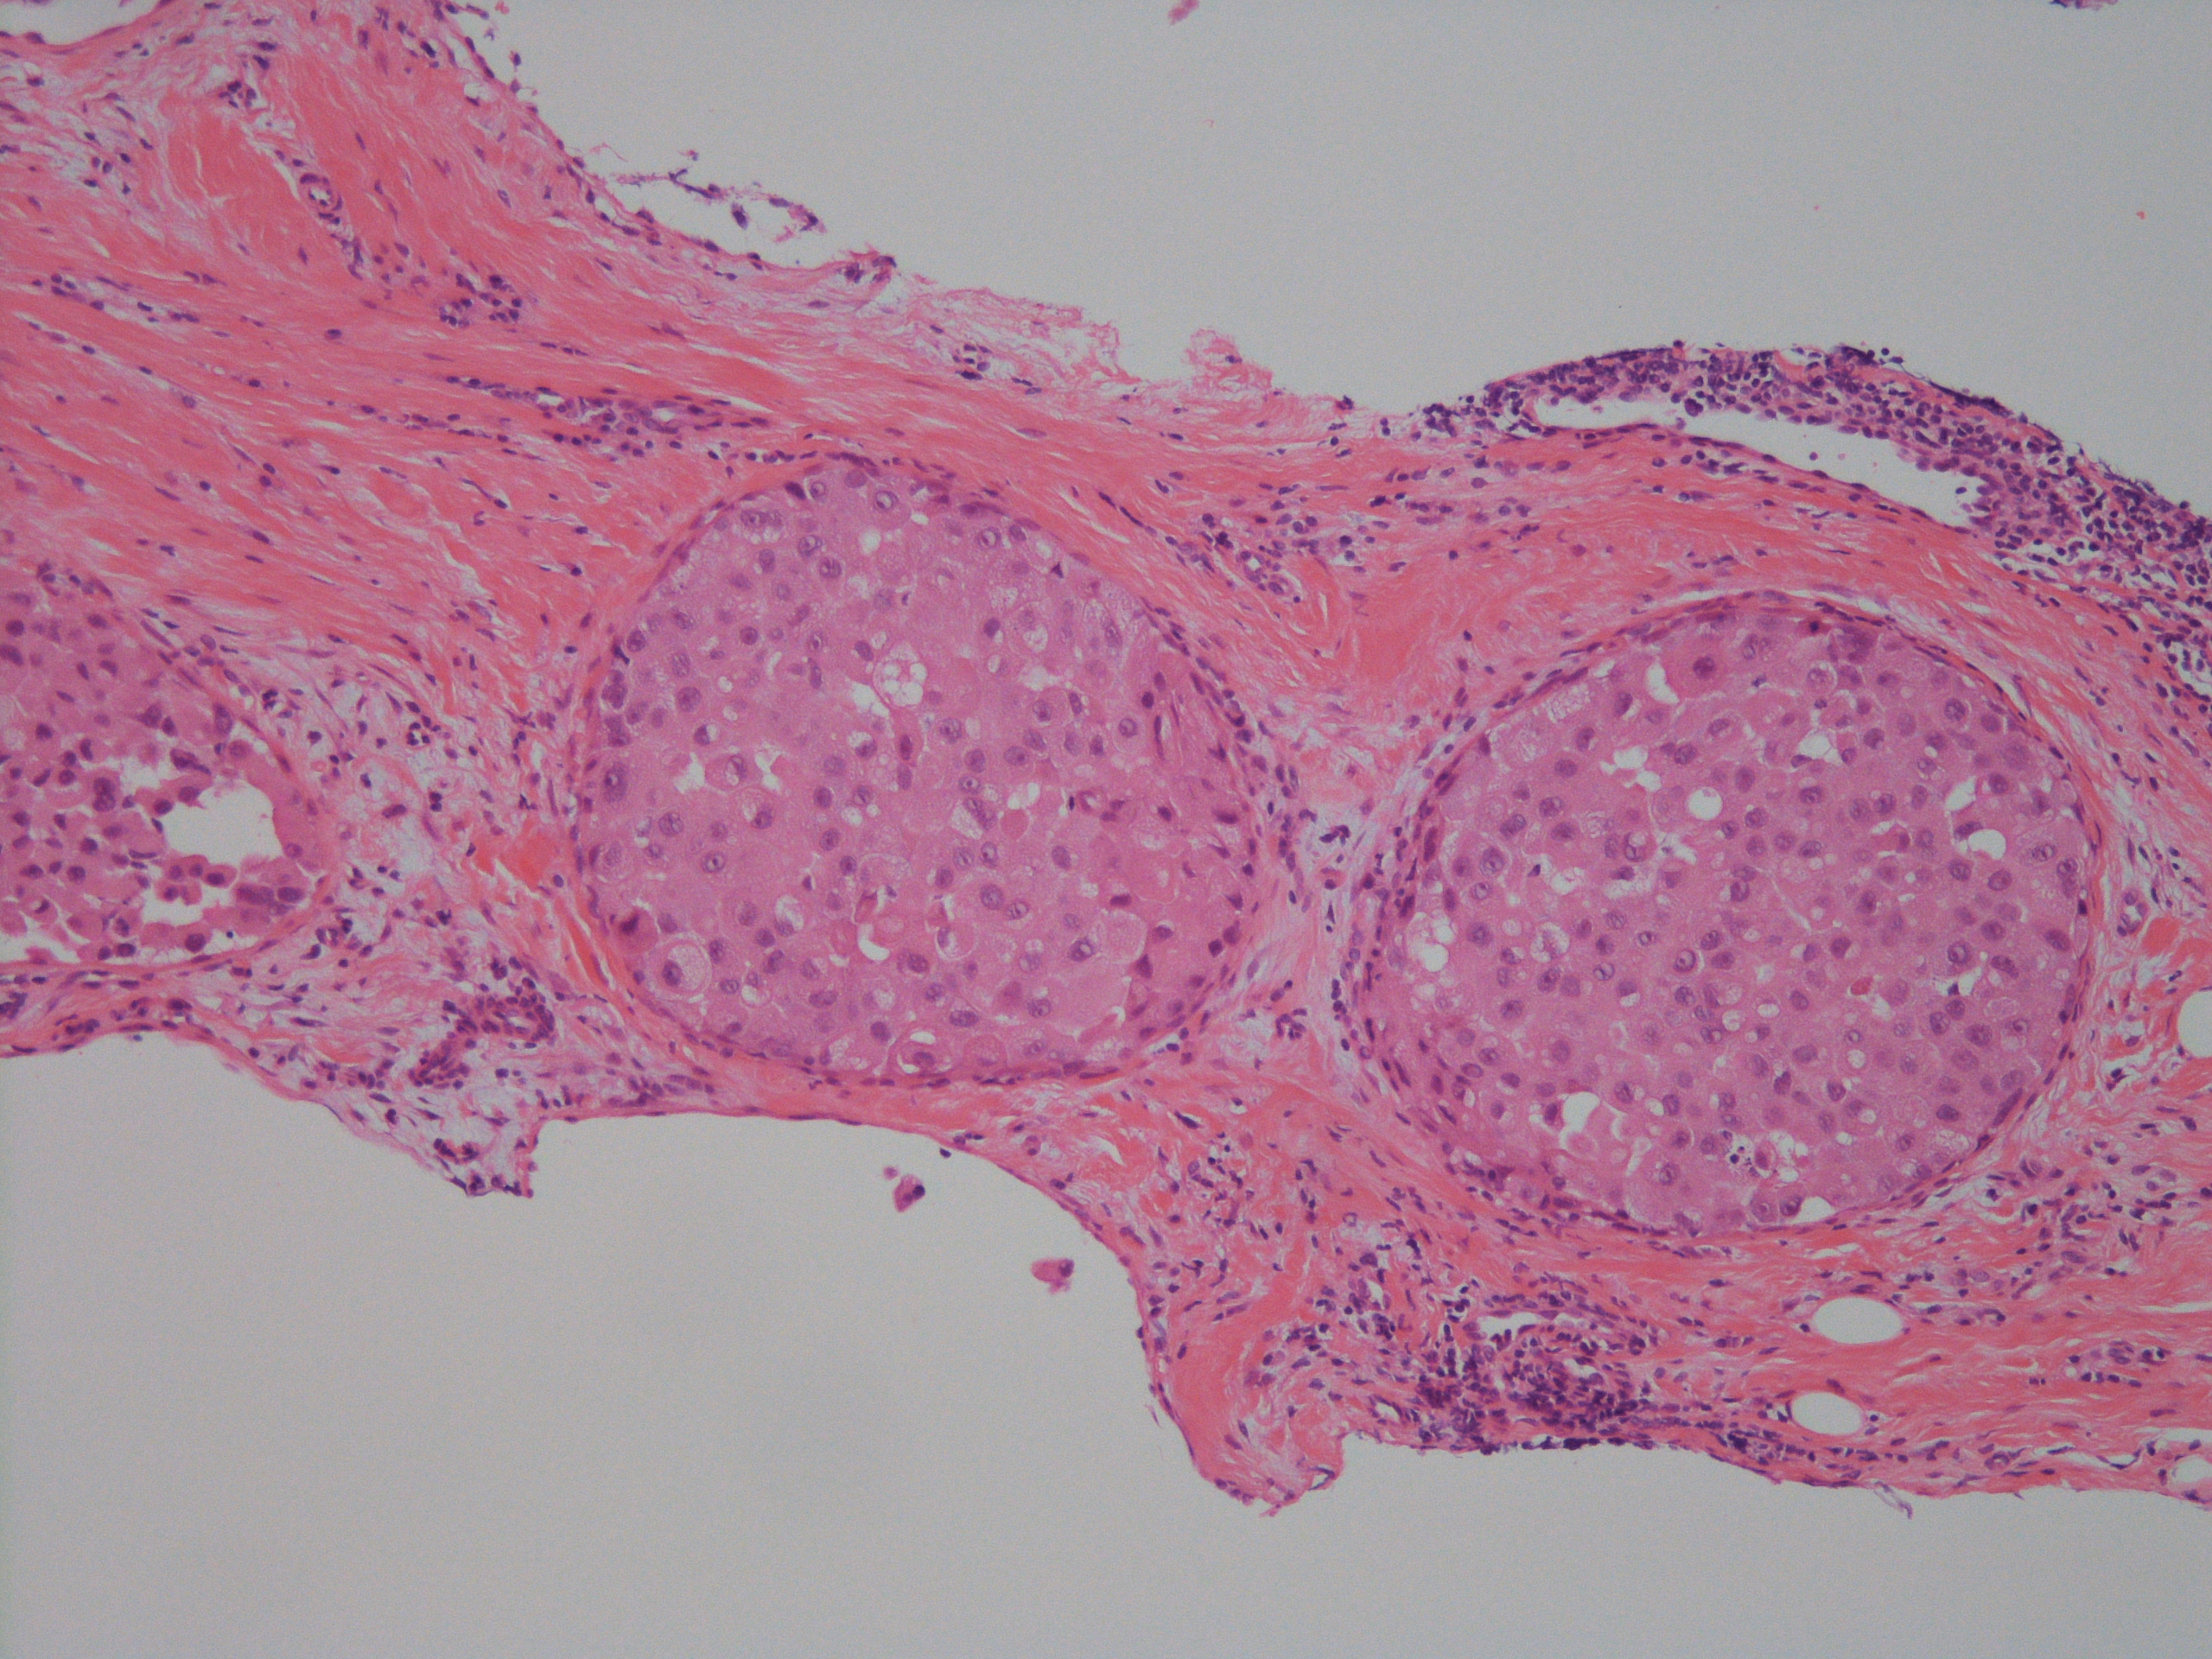

[組織所見]

組織では免疫染色も含め総合的に浸潤部は小葉癌(ER+、 HER2-)であったが、

乳管内癌成分においてもE-cadherinの染色性が減弱しており、非浸潤性乳管癌か非浸潤性小葉癌(多形型)か判断が難しいが、

乳管内癌成分はER-、HER2(3+)で形質発現はクリアカットに分かれ、最終的に非浸潤性乳管癌と診断された。